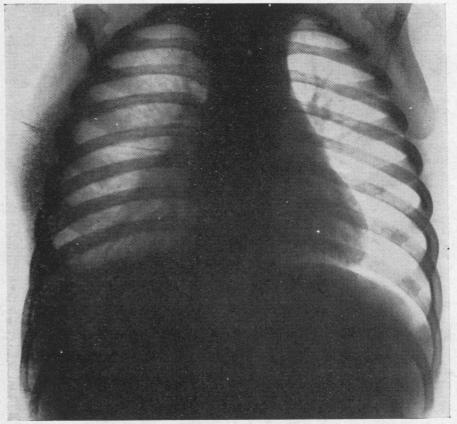

HARLEY H R S, DREW C E

Thorax. 1950 Jun;5(2):105-15. doi: 10.1136/thx.5.2.105.